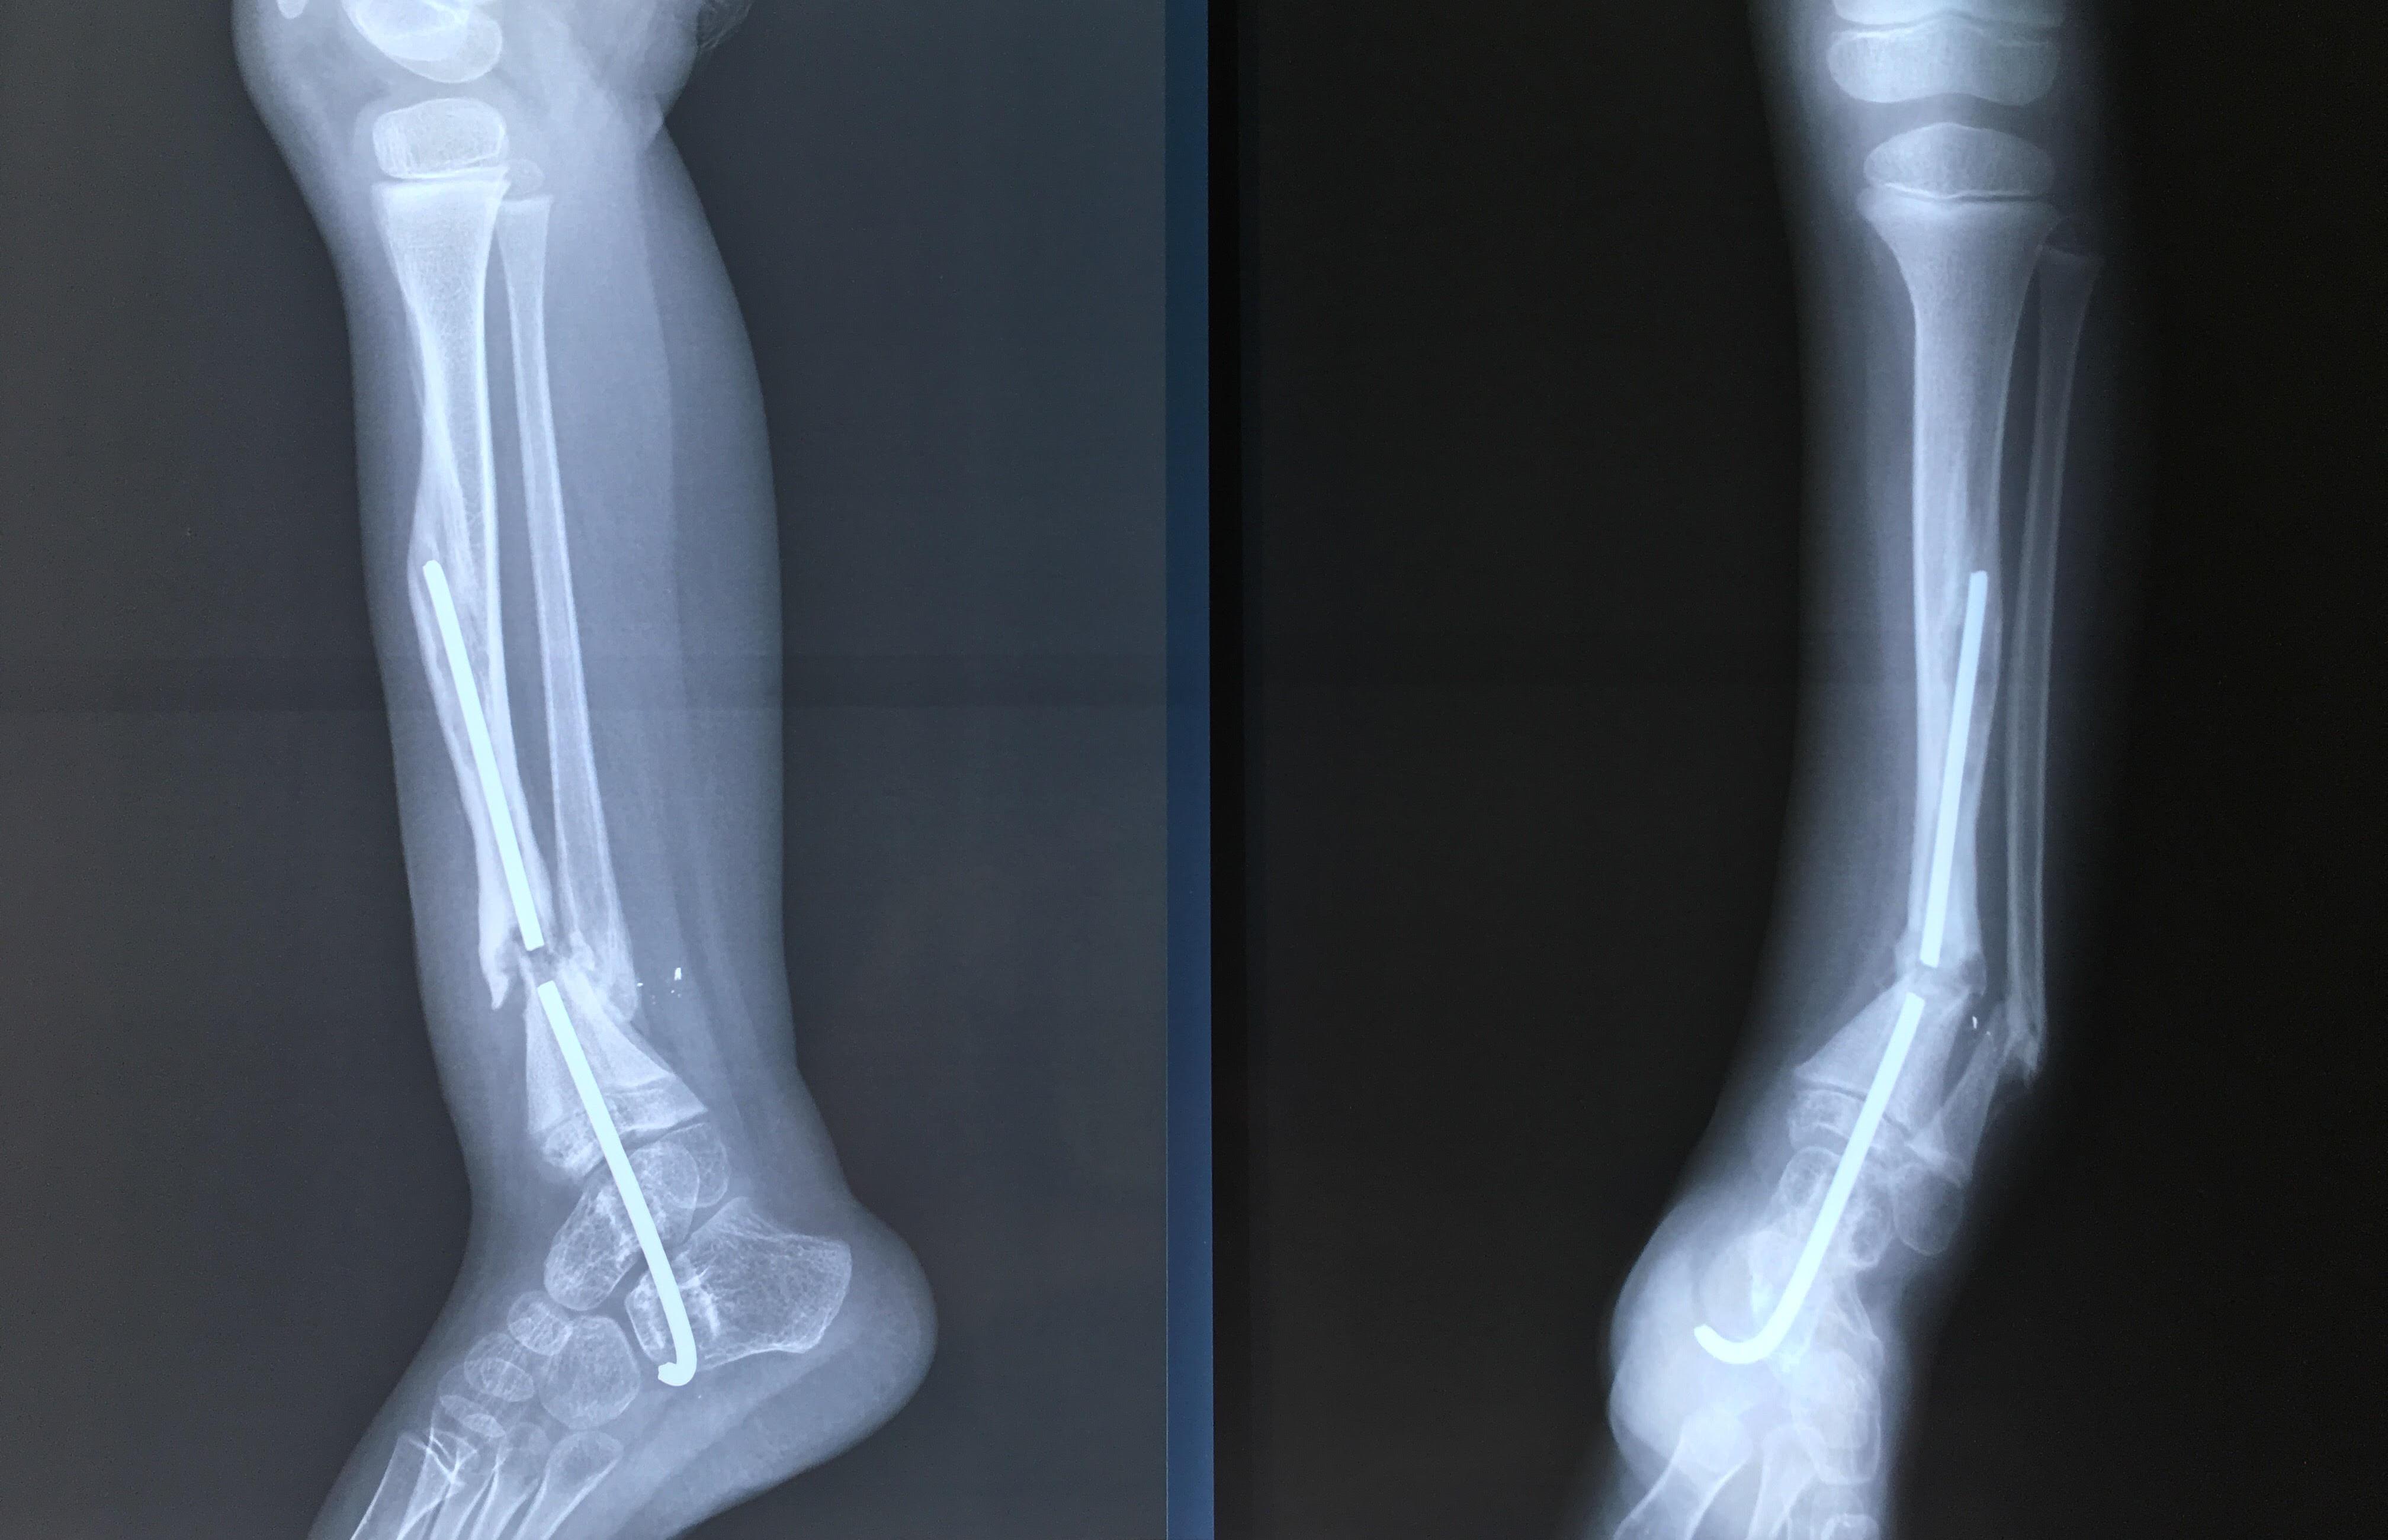

Phẫu thuật thành công ca bệnh hiếm gặp...khớp giả bẩm sinh xương chày

26/06/2019 17:00

Đã xem: 3735

Bệnh viện Chấn thương- Chỉnh hình Nghệ An, vừa phẫu thuật thành công cho bệnh nhi khớp giả bẩm sinh xương chày